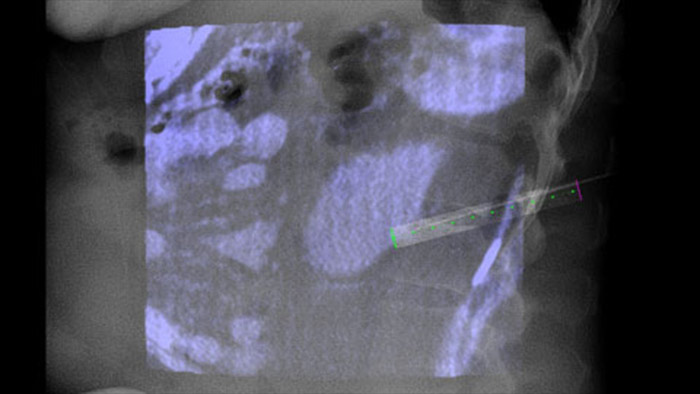

Технология XperGuide обеспечивает точный визуальный контроль при ведении иглы к исследуемой области в режиме реального времени, накладывая изображения предварительно запланированной траектории на рентгеноскопические изображения3.

Dual View позволяет наложить 3D-изображение, полученное до процедуры (КТ/МРТ/ПЭТ-КТ), на двойное КТ-подобное 3D-изображение, полученное во время процедуры, для улучшения визуализации поражений и получения важных данных, необходимых для планирования траектории иглы.